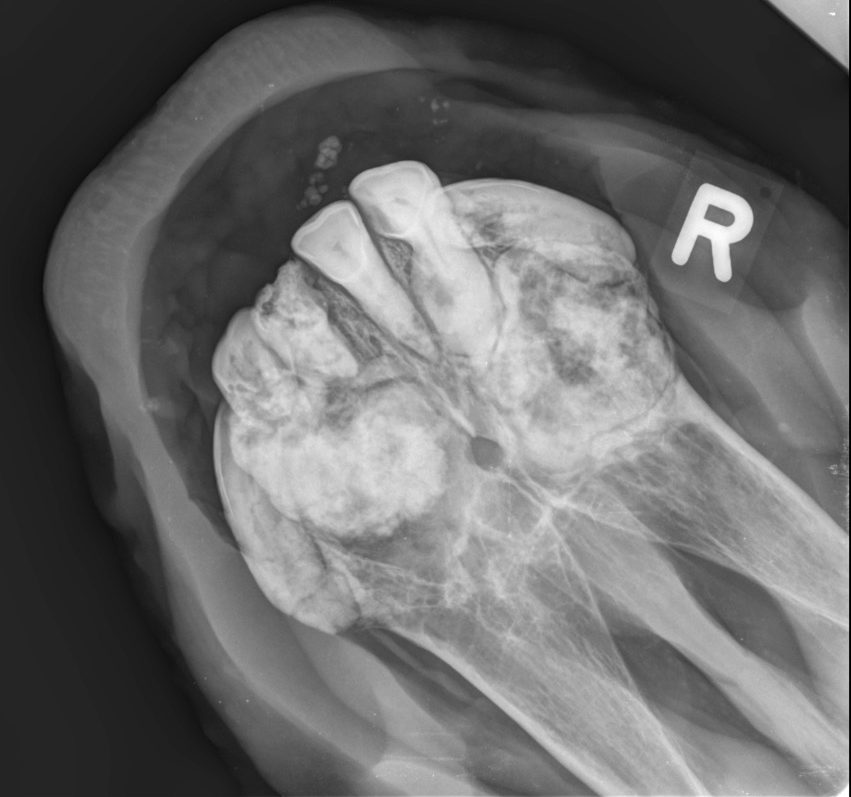

Bei diesem Krankheitsbild handelt es sich um einen schleichenden, zahnauflösenden Prozess, meist im Bereich der Schneidzähne. Es kommt zu einer Aktivierung von Zellen die das Zahnbein abbauen, was in einer Auflösung der Zahnsubstanz resultiert. Dies wiederum stimuliert Zellen, welche übermässig sogenanntes Reparaturzement auf die geschädigten Zahnbereiche ablagern. Es kommt zu den typischen, knolligen Veränderungen der Zahnfächer, was besonders auf Röntgenbildern eindrücklich erkennbar ist. Zudem sind klinisch eine Entzündung des Zahnfleisches, punktförmige Einblutungen und teilweise Fistelbildungen erkennbar.

Die Diagnose kann aufgrund einer Kombination der klinischen und radiologischen Befunde gestellt werden.